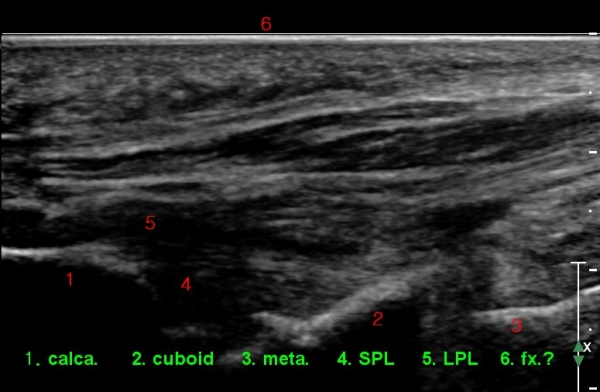

¹ß¸ñ ÇϺνÅÀüÁöÁö¶ì(inferior extensor retinaculum)ÀÇ frondiform Àδë Á¾´Ü¸é°Ë»ç ¹× Á·±Ùµ¿

Ⱦ´Ü¸é°Ë»ç¿¡¼­ °Å°ñ °æºÎ ¿ÜÃø °ß¿­°ñÀý, frondiformÀÎ´ë ½ÉÃþ ¼Õ»ó, ±×¸®°í Á·±Ùµ¿ °æºÎÀδë

(cervical ligament) ÆÄ¿­ÀÌ ÃßÁ¤µÈ´Ù(»çÁø 4, 5).